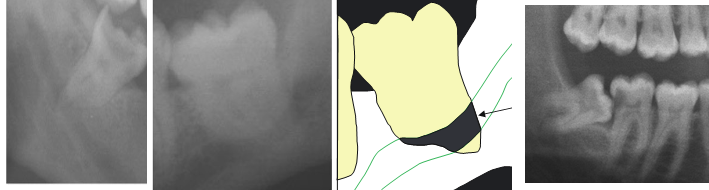

28

hardest impaction to extract?

distally impacted 8s need to remove distal bone

29

impaction of 8s?

LR8 - true vertical impaction LL8 - distal impaction

30

impaction of 8?

transverse impaction

31

LL8 aberrant position